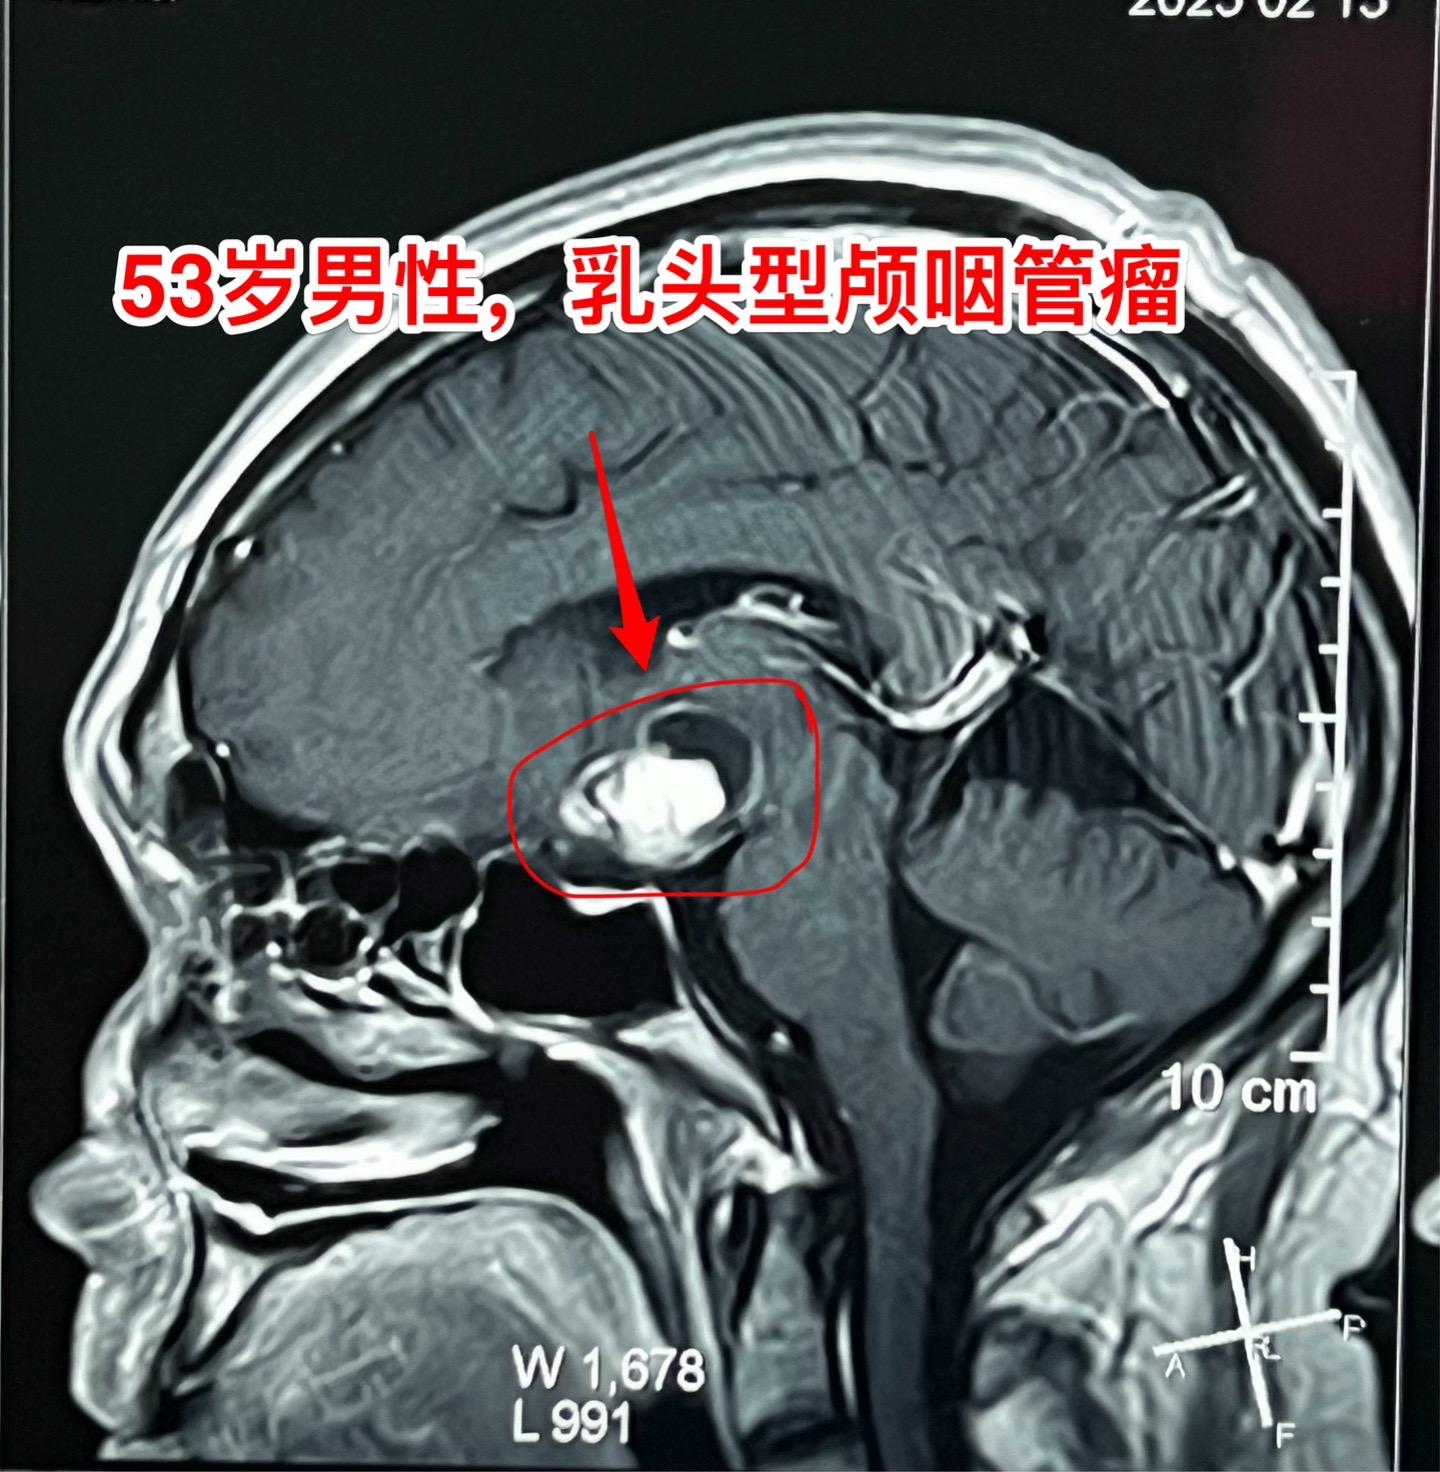

一天两个颅咽管瘤手术医生是很辛苦的 今天按计划作了两个颅咽管瘤手术。这是第二个病人,云南省文山州的警察,因记忆力差、爱睡觉、视力下降到医院检查发现了颅咽管瘤,是乳头型颅咽管瘤。 今天晚上九点多钟颅咽管瘤完全切除了,同时发现前交通动脉有个小动脉瘤,征得家人同意后作了动脉瘤夹闭术。期望病人一切都好!